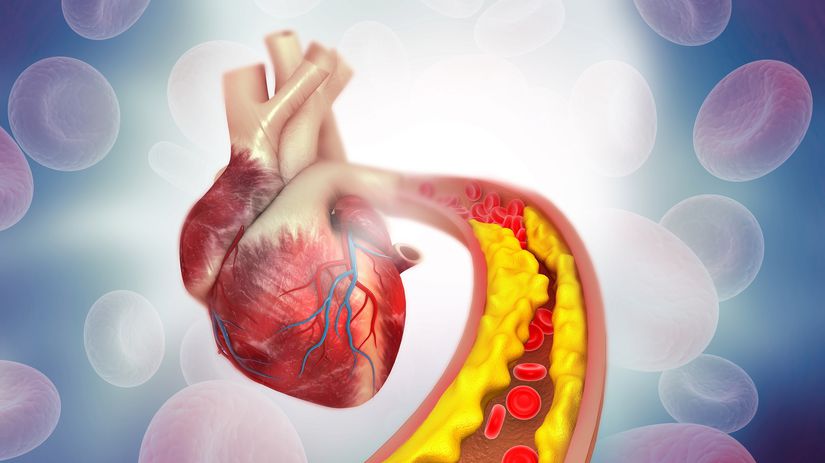

Cholesterol potrápi vaše cievy

S pribúdajúcim vekom sa na stenách ciev ukladá a hromadí stále viac cholesteru, to spôsobuje, že steny ciev sa stávajú krehkými a hrozí ich prasknutie, tiež sa v nich zvyšuje tlak, čo zaťažuje srdce, prípadne sa zvyšuje riziko vzniku zrazeniny, upchatia cievy (práve v znížením zúženom mieste cievy) a infarktu.

Hromadenie cholesteru podporuje nevhodná strava bohatá na tuky i fajčenie.